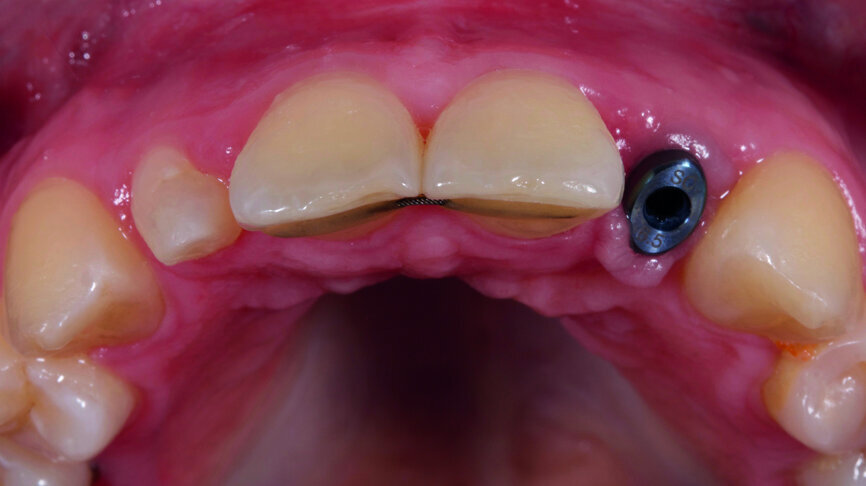

Fig. 8: Temporary crown was installed to support the formation of soft tissues.

Fig. 9: Temporary crown was installed to support the formation of soft tissues.

Fig. 10: Temporary crown was installed to support the formation of soft tissues.

Three months after the implant placement operation, the osseointegration of the implant fixture was completed. A temporary crown was fabricated on the implant from a VITA ENAMIC multiColor block to support the formation of soft tissues (Figs. 8–10). We improved the original design on the Straumann superstructure with gum contouring. On tooth #12, crown lengthening was performed with an electrocoagulator (Figs. 11–13).